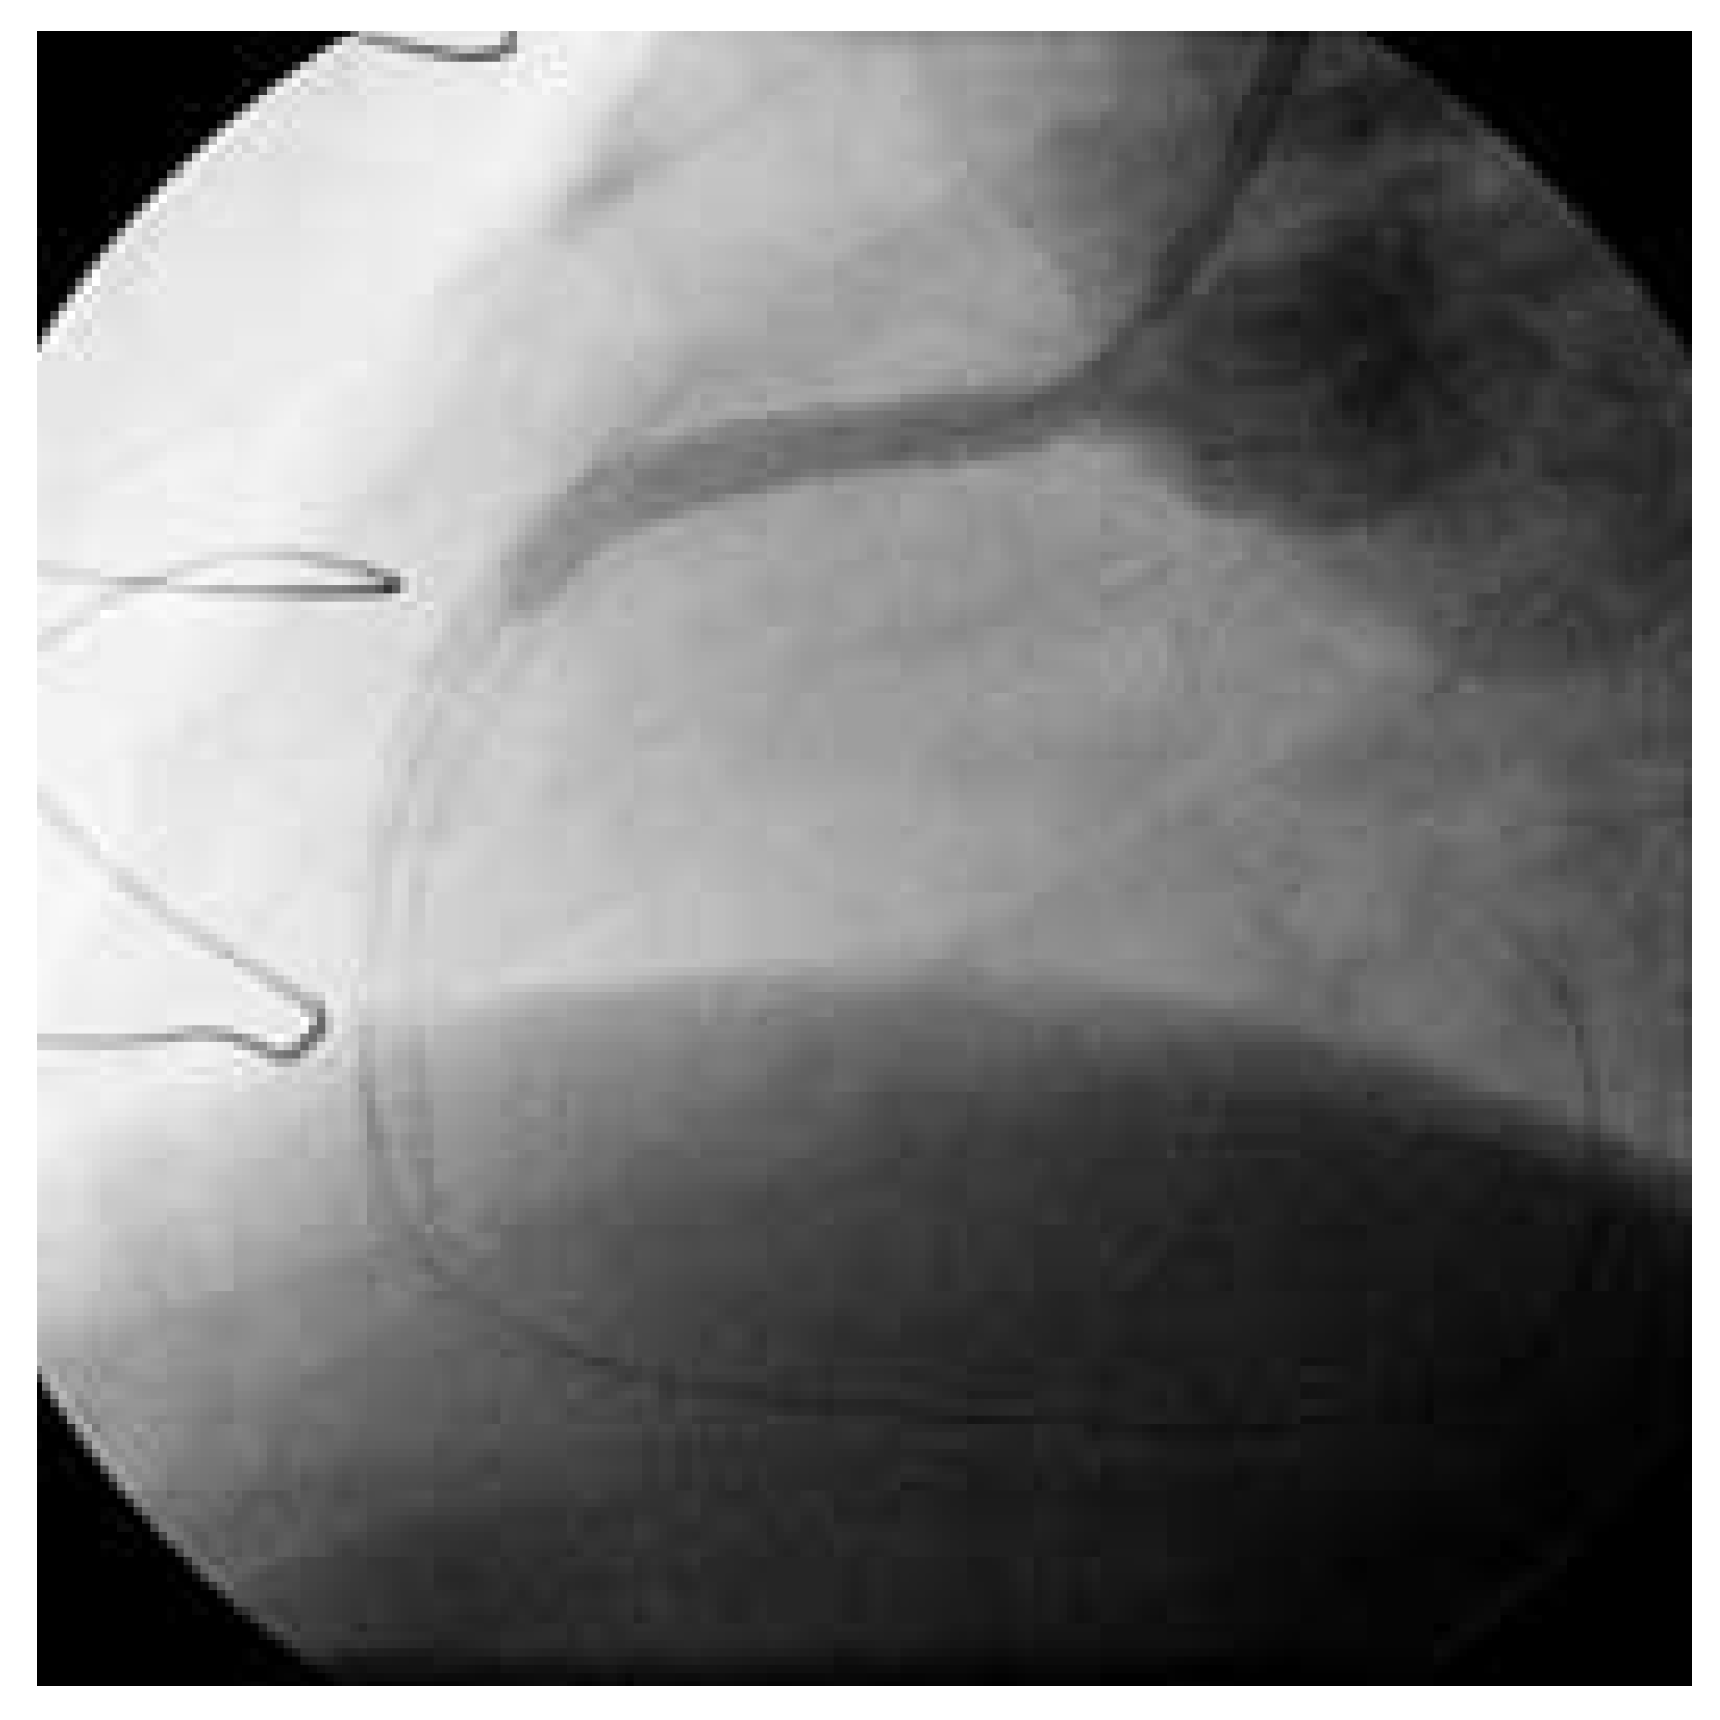

Abbildung 6. Nach Drahtpassage und trotz mehrfacher, langstrekkiger Ballon-Dilatation und intravaskulärer Nitrat-Gabe kommt kein antegrader Fuss im Venengraft zustande.

Beim zweiten Patienten handelt es sich um einen 72jährigen Patienten, welcher sich 1980 erstmals einer Bypass-Operation unterzog. 1988 wurde er reoperiert (LIMA zu RIVAund Diagonal-Ast, RIMA auf PLA des Ramus circumflexus, Vene zum RIVP der RCA und zum 2. PLA). Nach einer Prostata-Radikaloperation im Sommer 2003 kam es zu einer progredienten Angina pectoris CCS III. Trotz voll ausgebauter antiischämischer Behandlung traten immer häufigere Episoden von Ruhe-Angor auf. Im Februar 2004 zeigte die Koronarangiographie einwandfreie arterielle Bypass-Verhältnisse und einen proximalen, langstrekkigen Verschluss des Venengraftes (Abb. 5). Nach Drahtpassage und mehrfacher, langstreckiger Ballondilatation und intravaskulärer Nitrat-Gabe kommt kein antegrader Fuss zustande (Abb. 6). Erst nach mehreren Passagen mit dem Thrombusaspirationskatheter kommt der Venenbypass und die angeschlossenen Gefässe zur Darstellung. Das Endresultat nach Stenteinlage (Abb. 7 und 8) ist sehr zufriedenstellend. Der Patient ist seit dem Eingriff beschwerdefrei.